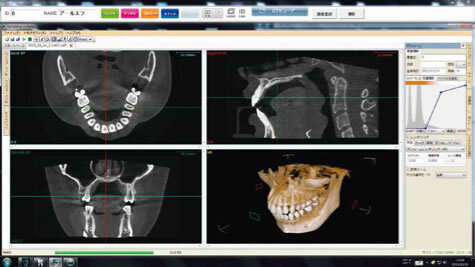

③レントゲン撮影

(パントモX線・頭部X線・頭部X線規格写真正面側面など)

④3DCT